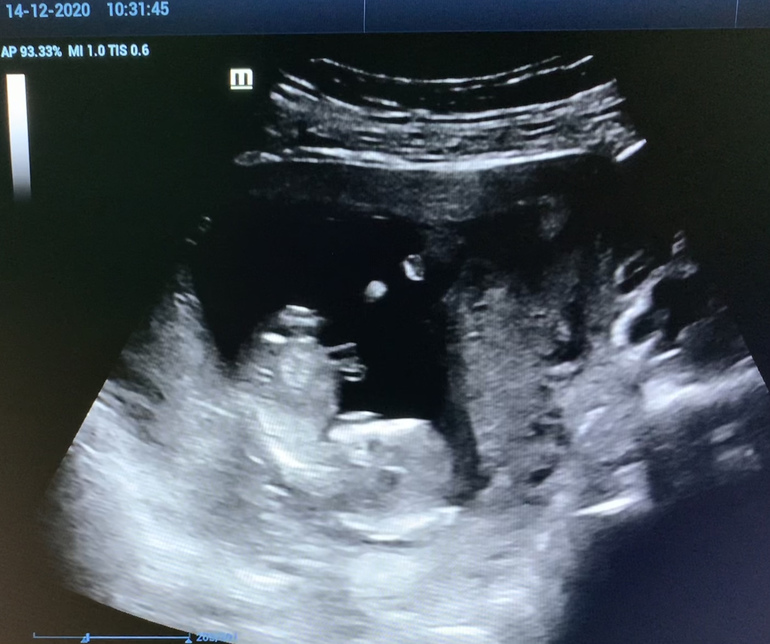

В прошлый понедельник сдавала кровь, сегодня делали УЗИ, кровь уже была готова. Срок сегодня 12 нед. 5 дней по месячным. УЗИ-врач сказал риски низкие, ребёнок развивается хорошо в соответствии со сроком. ПДР поставили на 23.06.2020. Чувство счастья не покидало меня весь день! Врач была приятная, без лица кирпичом. На экране показали малявочку и разрешили сфоткать на телефон.